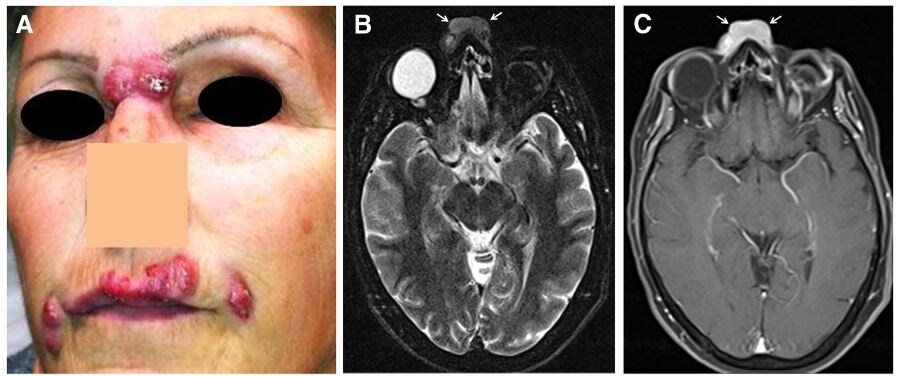

Как и у любой процедуры, проникающей сквозь кожу и ткани, у наполнителей есть осложнения. К краткосрочным относятся кровотечения, синяки, инфекции, покраснение в месте инъекции и отек, которые обычно проходят в течение нескольких дней. Риск введения не в то место присутствует всегда. А вот о долгосрочных осложнениях почти не говорят. Ведь какие осложнения, если они должны сами рассасываться? Однако через шесть месяцев могут появляться другие осложнения, включая образование абсцессов и гранулем из инородных тел, инфекции, перемещение препарата и перекрестные реакции между различными препаратами, введенными в соседние места. Это приводит к отеку, изменению цвета кожи, образованию шишек и в конечном итоге язв.

Поэтому, когда у людей, делавших уколы красоты десять лет назад, МРТ показывало, что наполнители все еще там, это неудивительно. Особенно это заметно в области вокруг глаз. Другие исследования нашли наполнители, введенные 2, 6 и 12 лет назад. Причем испытуемые отрицали, что когда-либо их делали, пока им не показали снимки, где наполнители все так же были на своих местах. Самое интересное — это то, что наполнители могут перемещаться.

Di Girolamo, Marco, et al. "MRI in the evaluation of facial dermal fillers in normal and complicated cases." European radiology 25 (2015): 1431-1442.

Mundada, Pravin, et al. "Injectable facial fillers: imaging features, complications, and diagnostic pitfalls at MRI and PET CT." Insights into imaging 8 (2017): 557-572.

Master, Mobin. "Hyaluronic acid filler longevity and localization: magnetic resonance imaging evidence." Plastic and Reconstructive Surgery 147.1 (2021): 50e-53e.

Tal, Sigal, et al. "MRI in detecting facial cosmetic injectable fillers." Head & face medicine 12 (2016): 1-7.